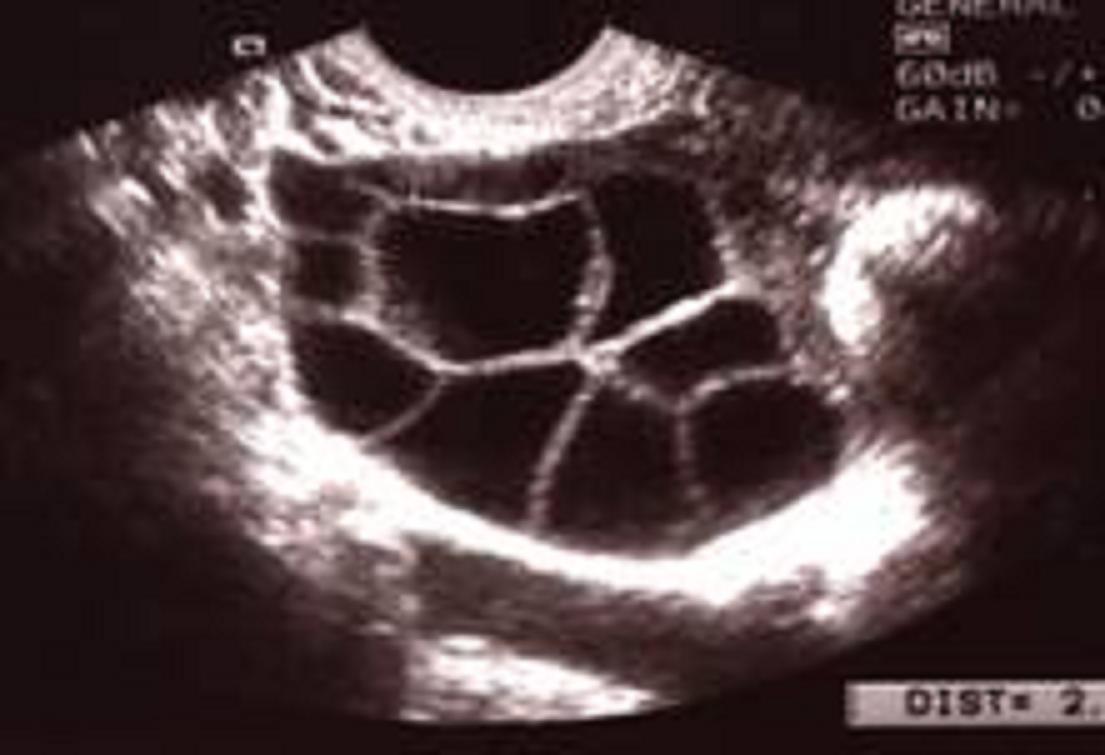

Échographie par voie endovaginale d'un ovaire stimulé en vue de FIV